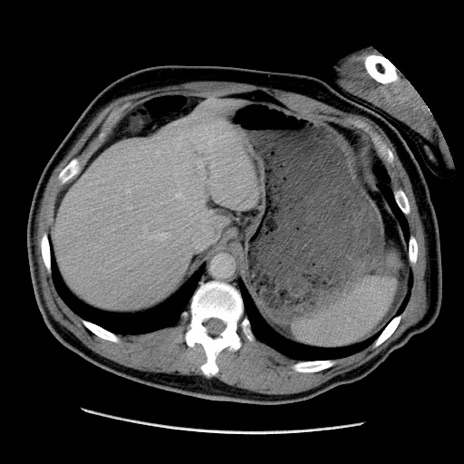

症例22(横断像)

【症例】50歳代男性

【主訴】腹痛

【現病歴】AVMからの被殻出血のため回復期リハ病棟入院中。 本日午後3時頃急に下腹部痛が出現した。

【既往歴】AVM、被殻出血、虫垂炎、高血圧

【身体所見】意識晴明、左半身不全麻痺、会話の理解は良好、36.5°C、腹部:膨隆、全体に板状硬、下腹部正中に圧痛点あり、反跳痛-、筋性防御不明、右下腹部にope scar

【データ】WBC 9400、CRP 0.06